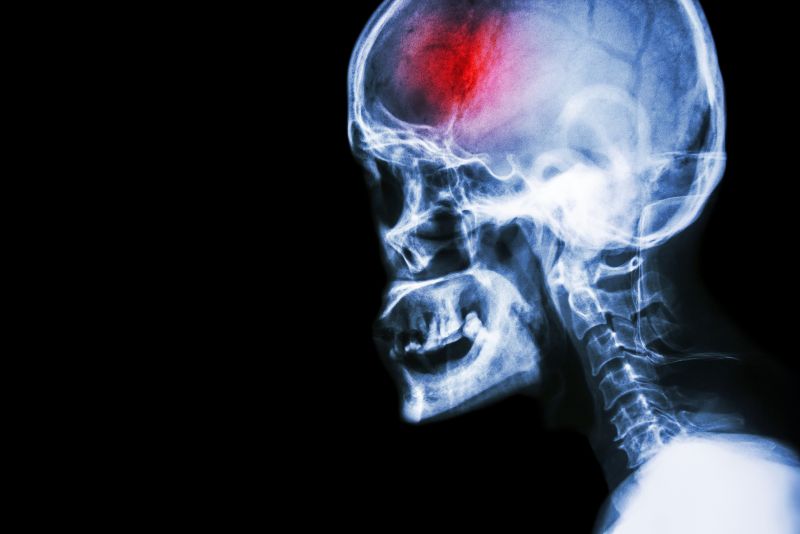

Physical therapy in Columbus for Stroke Rehabilitation

Head X-ray